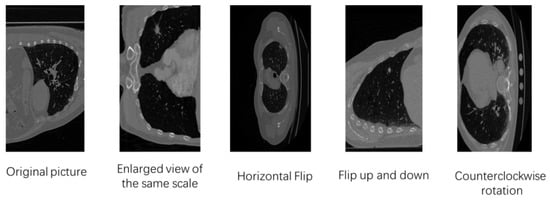

At the beginning of the segmentation experiments, we found that the loss quickly goes to zero. After repeated changes, the loss still showed no improvement. Finally, we determined that the problem was over-fitting. To solve this sticky problem, we employed data augmentation techniques to generate more similar data from restricted datasets, enrich the distribution of training data, and improve the model’s generalizability. We used the data augmentation library to rotate the picture counterclockwise randomly, flip it horizontally, flip it up and down, and enlarge the image at the same scale. The data augmentation image styles are shown in Figure 8.

Figure 8.

A sample of the data augmentation images.